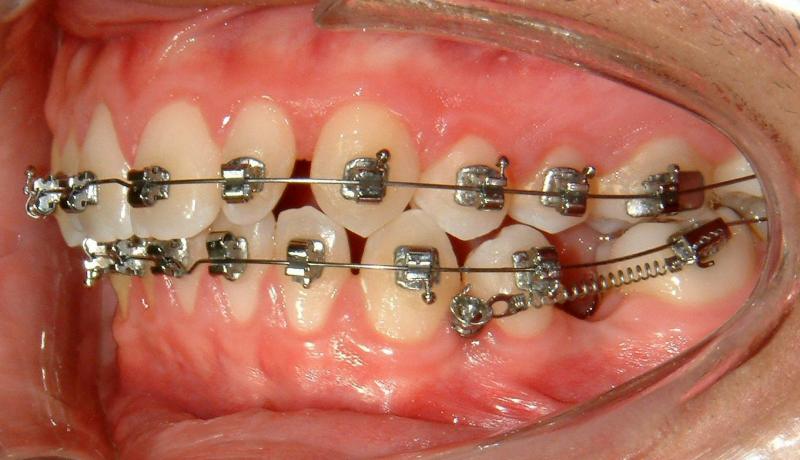

Fig. 6. Immediate loading for TAD (activated)

© Copyright 2007-2014, Vu Orthodontics. All rights reserved.

It can be seen that Figure 6 shows immediate loading with light activation which is necessary for bone modeling.

Fig. 7. Loading with NiTi spring (more effective)

The TAD is used as an absolute anchorage to protract LL6 without side effect. (The lower left canine will be moved forward later to achieve Class I canines.) An alternative mechanics may be used with a power arm to achieve a slightly more horizontal force but a bit complicated and less comfort (for the patient).